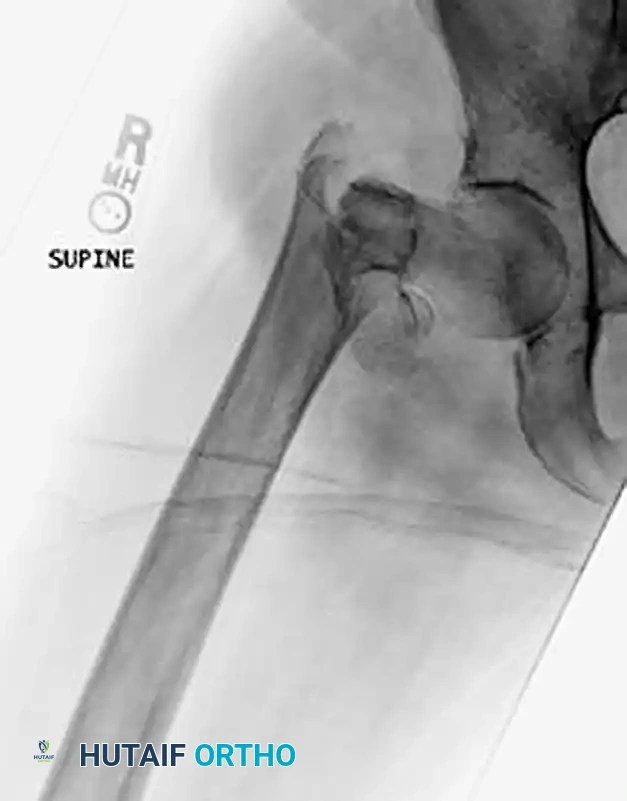

CLOSED REDUCTION MANEUVERS

Surgical Warning: Never proceed with the surgical incision until an acceptable closed reduction is confirmed on both AP and lateral fluoroscopic views. A poorly reduced fracture cannot be salvaged by a perfectly placed implant.

- Standard Reduction: Reduction of the affected extremity is typically achieved through longitudinal traction followed by internal rotation. The internal rotation corrects the external rotation deformity caused by the short external rotators and gravity, bringing the femoral neck parallel to the floor.

- Correcting Sagittal Deformity: The most common sagittal plane deformity is a posterior sag of the fracture site. This may require correction via an anteriorly applied force (e.g., a crutch or a specialized reduction tool placed under the posterior thigh) to lift the distal fragment before finalizing the reduction with traction and internal rotation.

- Fluoroscopic Scrutiny: Carefully scrutinize the images to rule out varus deformity, posterior sag, and excessive internal rotation. A slight valgus reduction is biomechanically superior to any degree of varus.